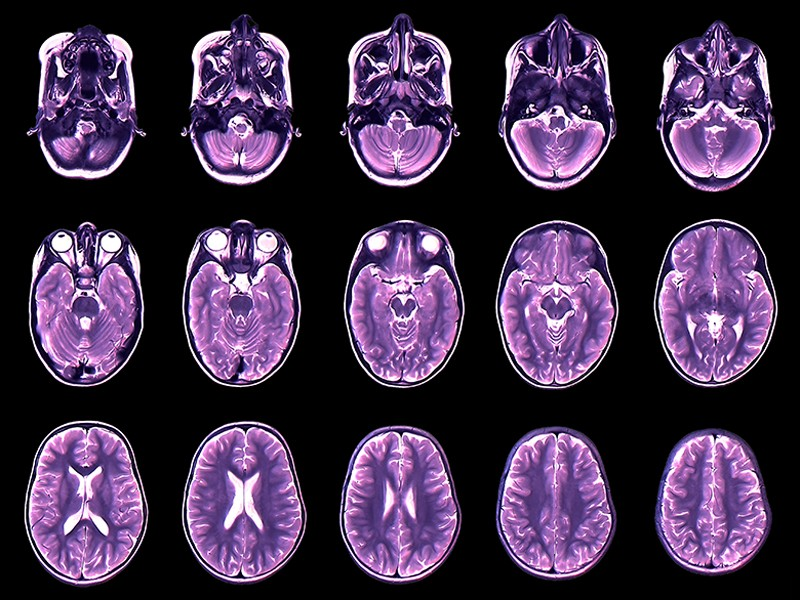

Desde que hacia fines del siglo XVIII comenzaran a publicarse tablas que cuantificaban distintas medidas corporales, como la altura o la circunferencia de la cabeza, con el paso de los años, estas mediciones se transformaron en una guía pediátrica de enorme ayuda para comprender de mejor manera el desarrollo de los niños en período de crecimiento y hallar anomalías cuando las había. Somos una especie con muchos factores en común, pero también hay una enorme variabilidad y cantidad de matices en nuestro desarrollo biológico. Es por esto que la novedosa biblioteca de mapeos cerebrales, la más grande jamás compendiada, ayudará enormemente a la comprensión del ritmo de crecimiento del cerebro.

Para lograr esta titánica tarea Jakob Seidlitz reunió más de 120.000 escáneres cerebrales para crear los primeros gráficos de crecimiento completos del desarrollo cerebral. La muestra más joven pertenece a un feto tras dieciséis semanas de su concepción, y la más vieja a la de un centenario. El arco completo de la vida humana. Los gráficos muestran visualmente cómo los cerebros humanos se expanden rápidamente al principio de la vida y luego se encogen lentamente con la edad.

El conjunto de datos sirve para esbozar una secuencia animada del recorrido del cerebro a lo largo de la vida humana. Con un detalle sin precedentes, captó cómo el cerebro "medio" crece velozmente durante la infancia, madura y declina con la edad, y comparó el proceso medio con el de las personas afectadas por enfermedades como el Alzheimer. Uno de los puntos más relevantes es que el estudio trató de abarcar las diferencias individuales. En lugar de una única línea nítida que represente la trayectoria de crecimiento del cerebro, los resultados son más bien múltiples bocetos en la misma dirección, cada uno único, pero que juntos forman un boceto detallado de los aspectos más destacados del desarrollo cerebral.

Si quieres los números exactos del estudio aquí van: el equipo reunió 123.894 escaneos de resonancia magnética de 101.457 personas. Los escáneres incluían cerebros de personas neurotípicas, así como de personas con diversas afecciones médicas, como la enfermedad de Alzheimer, y diferencias neurocognitivas, como el trastorno del espectro autista. Los investigadores utilizaron modelos estadísticos para extraer información de las imágenes y garantizar que los escaneos fueran directamente comparables, independientemente del tipo de máquina de IRM que se hubiera utilizado.